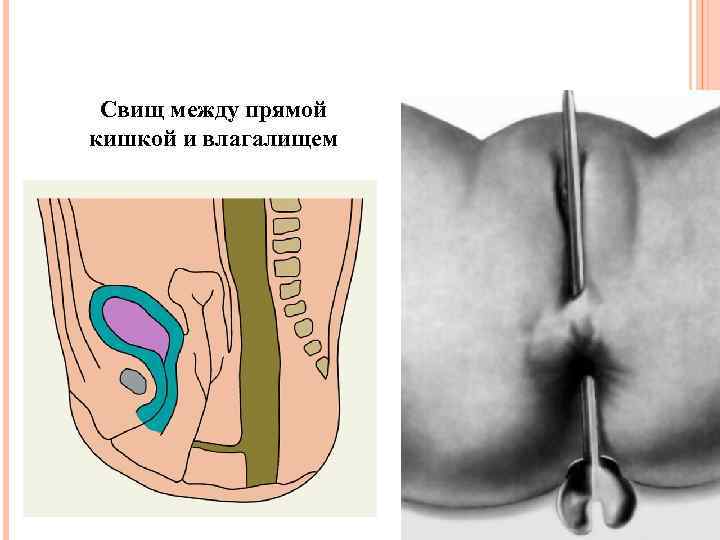

Свищ между прямой кишкой и влагалищем

Свищ между прямой кишкой и влагалищем